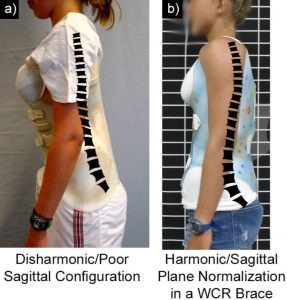

2. زيادة التقوس القطني داخل الحزام (In-brace Lordosis)

تشير الدراسات إلى أن زيادة التقوس القطني الصحي أثناء ارتداء الحزام ترتبط بنتائج أفضل.

والسبب في ذلك أن التوازن السهمي الجيد يسمح للحزام بتوزيع الضغط بشكل أكثر فعالية.

بالتالي، الحزام الذي يسمح بالحفاظ على التقوس الطبيعي للظهر يكون أكثر نجاحًا من الحزام الصلب المفرط.

3. التقوس السهمي قبل العلاج

الأطفال الذين يعانون من نقص في التقوس الطبيعي لمنطقة منتصف الظهر (Hypothoracolumbar Profile) قد يستفيدون أكثر من الحزام إذا كان لديهم تقوس قطني جيد قبل العلاج.

الحزام الفعّال هو الذي:

يحافظ على التقوس الطبيعي للظهر

يتكيف مع شكل القفص الصدري

لا يسبب ضغطًا مفرطًا يعيق الالتزام

لذلك، الأحزمة المصممة خصيصًا بناءً على التحليل ثلاثي الأبعاد تحقق نتائج أفضل من الأحزمة التقليدية العامة.